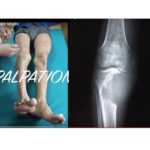

Examination of A bony Swelling